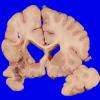

VASCULAR

Infarct, Tract Degeneration, illustrative case (2)